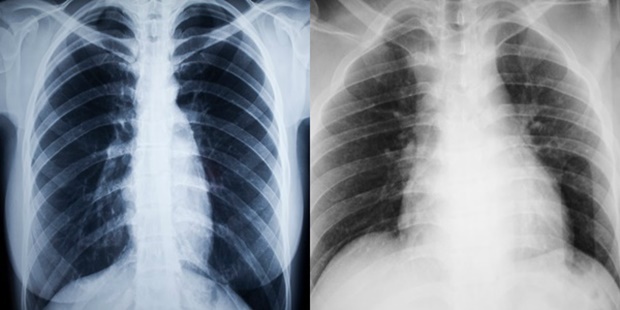

Πώς είναι στην πραγματικότητα η βλάβη στους πνεύμονες από το κάπνισμα

Εδώ βλέπετε την ακτινογραφία ενός ατόμου που δεν καπνίζει και έχει υγιείς πνεύμονες (αριστερά) και την αντίστοιχη ακτινογραφία ενός ατόμου που είναι χρόνιος καπνιστής και έχει κατεστραμμένους πνεύμονες (δεξιά).

Το κάπνισμα καταστρέφει τον πνευμονικό ιστό και αυτό είναι άμεσα ορατό στον καθένα. Ο καπνός από το τσιγάρο περιέχει περίπου 4.000 χημικές ουσίες, συμπεριλαμβανομένου του μονοξειδίου του άνθρακα. Αυτό δυσχεραίνει πολύ την λειτουργία των πνευμόνων και εμποδίζει το πολύτιμο οξυγόνο να κυκλοφορεί σωστά μέσα στο σώμα. Οι χημικές ουσίες στον καπνό του τσιγάρου ερεθίζουν και προκαλούν φλεγμονή στους αεραγωγούς και τους πνεύμονες.